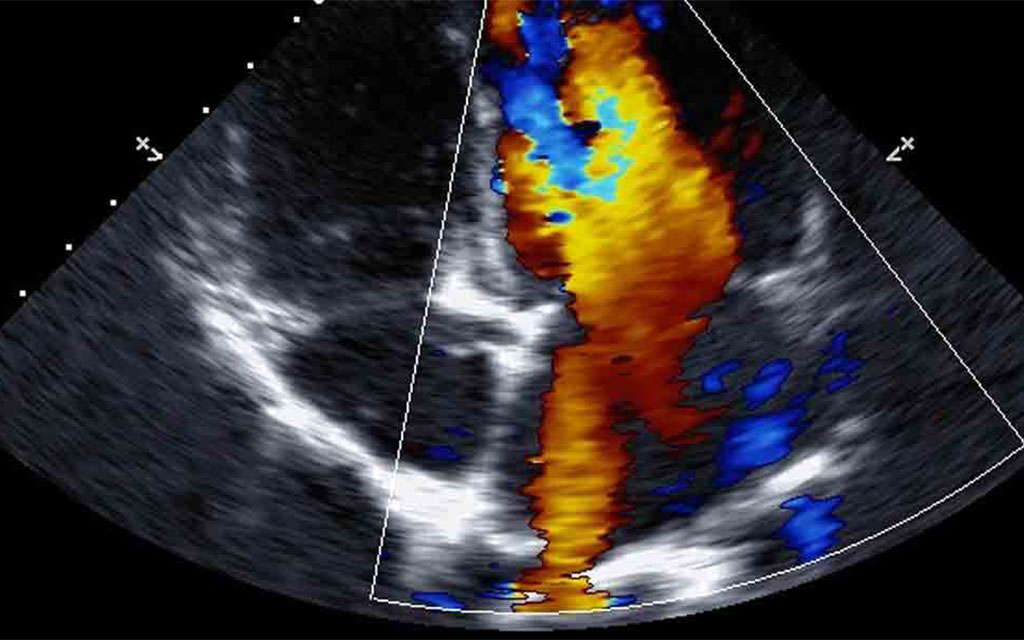

Per lo svolgimento di questa particolare ecografia si è soliti impiegare un dispositivo provvisto di una sonda che, emettendo un fascio di ultrasuoni, irradia i tessuti del corpo dell’area coinvolta dallo screening medico e genera dei fasci riflessi, detti echi di rimando, che la stessa sonda si occupa di reintercettare. A differenza di quanto avviene con l’Ecografia Doppler normale, con l’Ecocolordoppler è possibile studiare la dinamica del sangue del paziente mediante l’applicazione di una diversa colorazione ai vari flussi ematici che avvengono all’interno della parte del corpo esaminata.